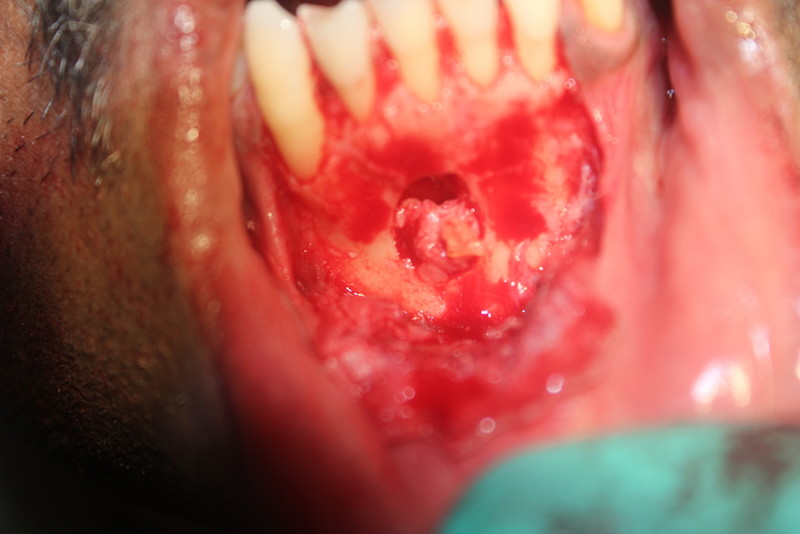

Apicoectomy